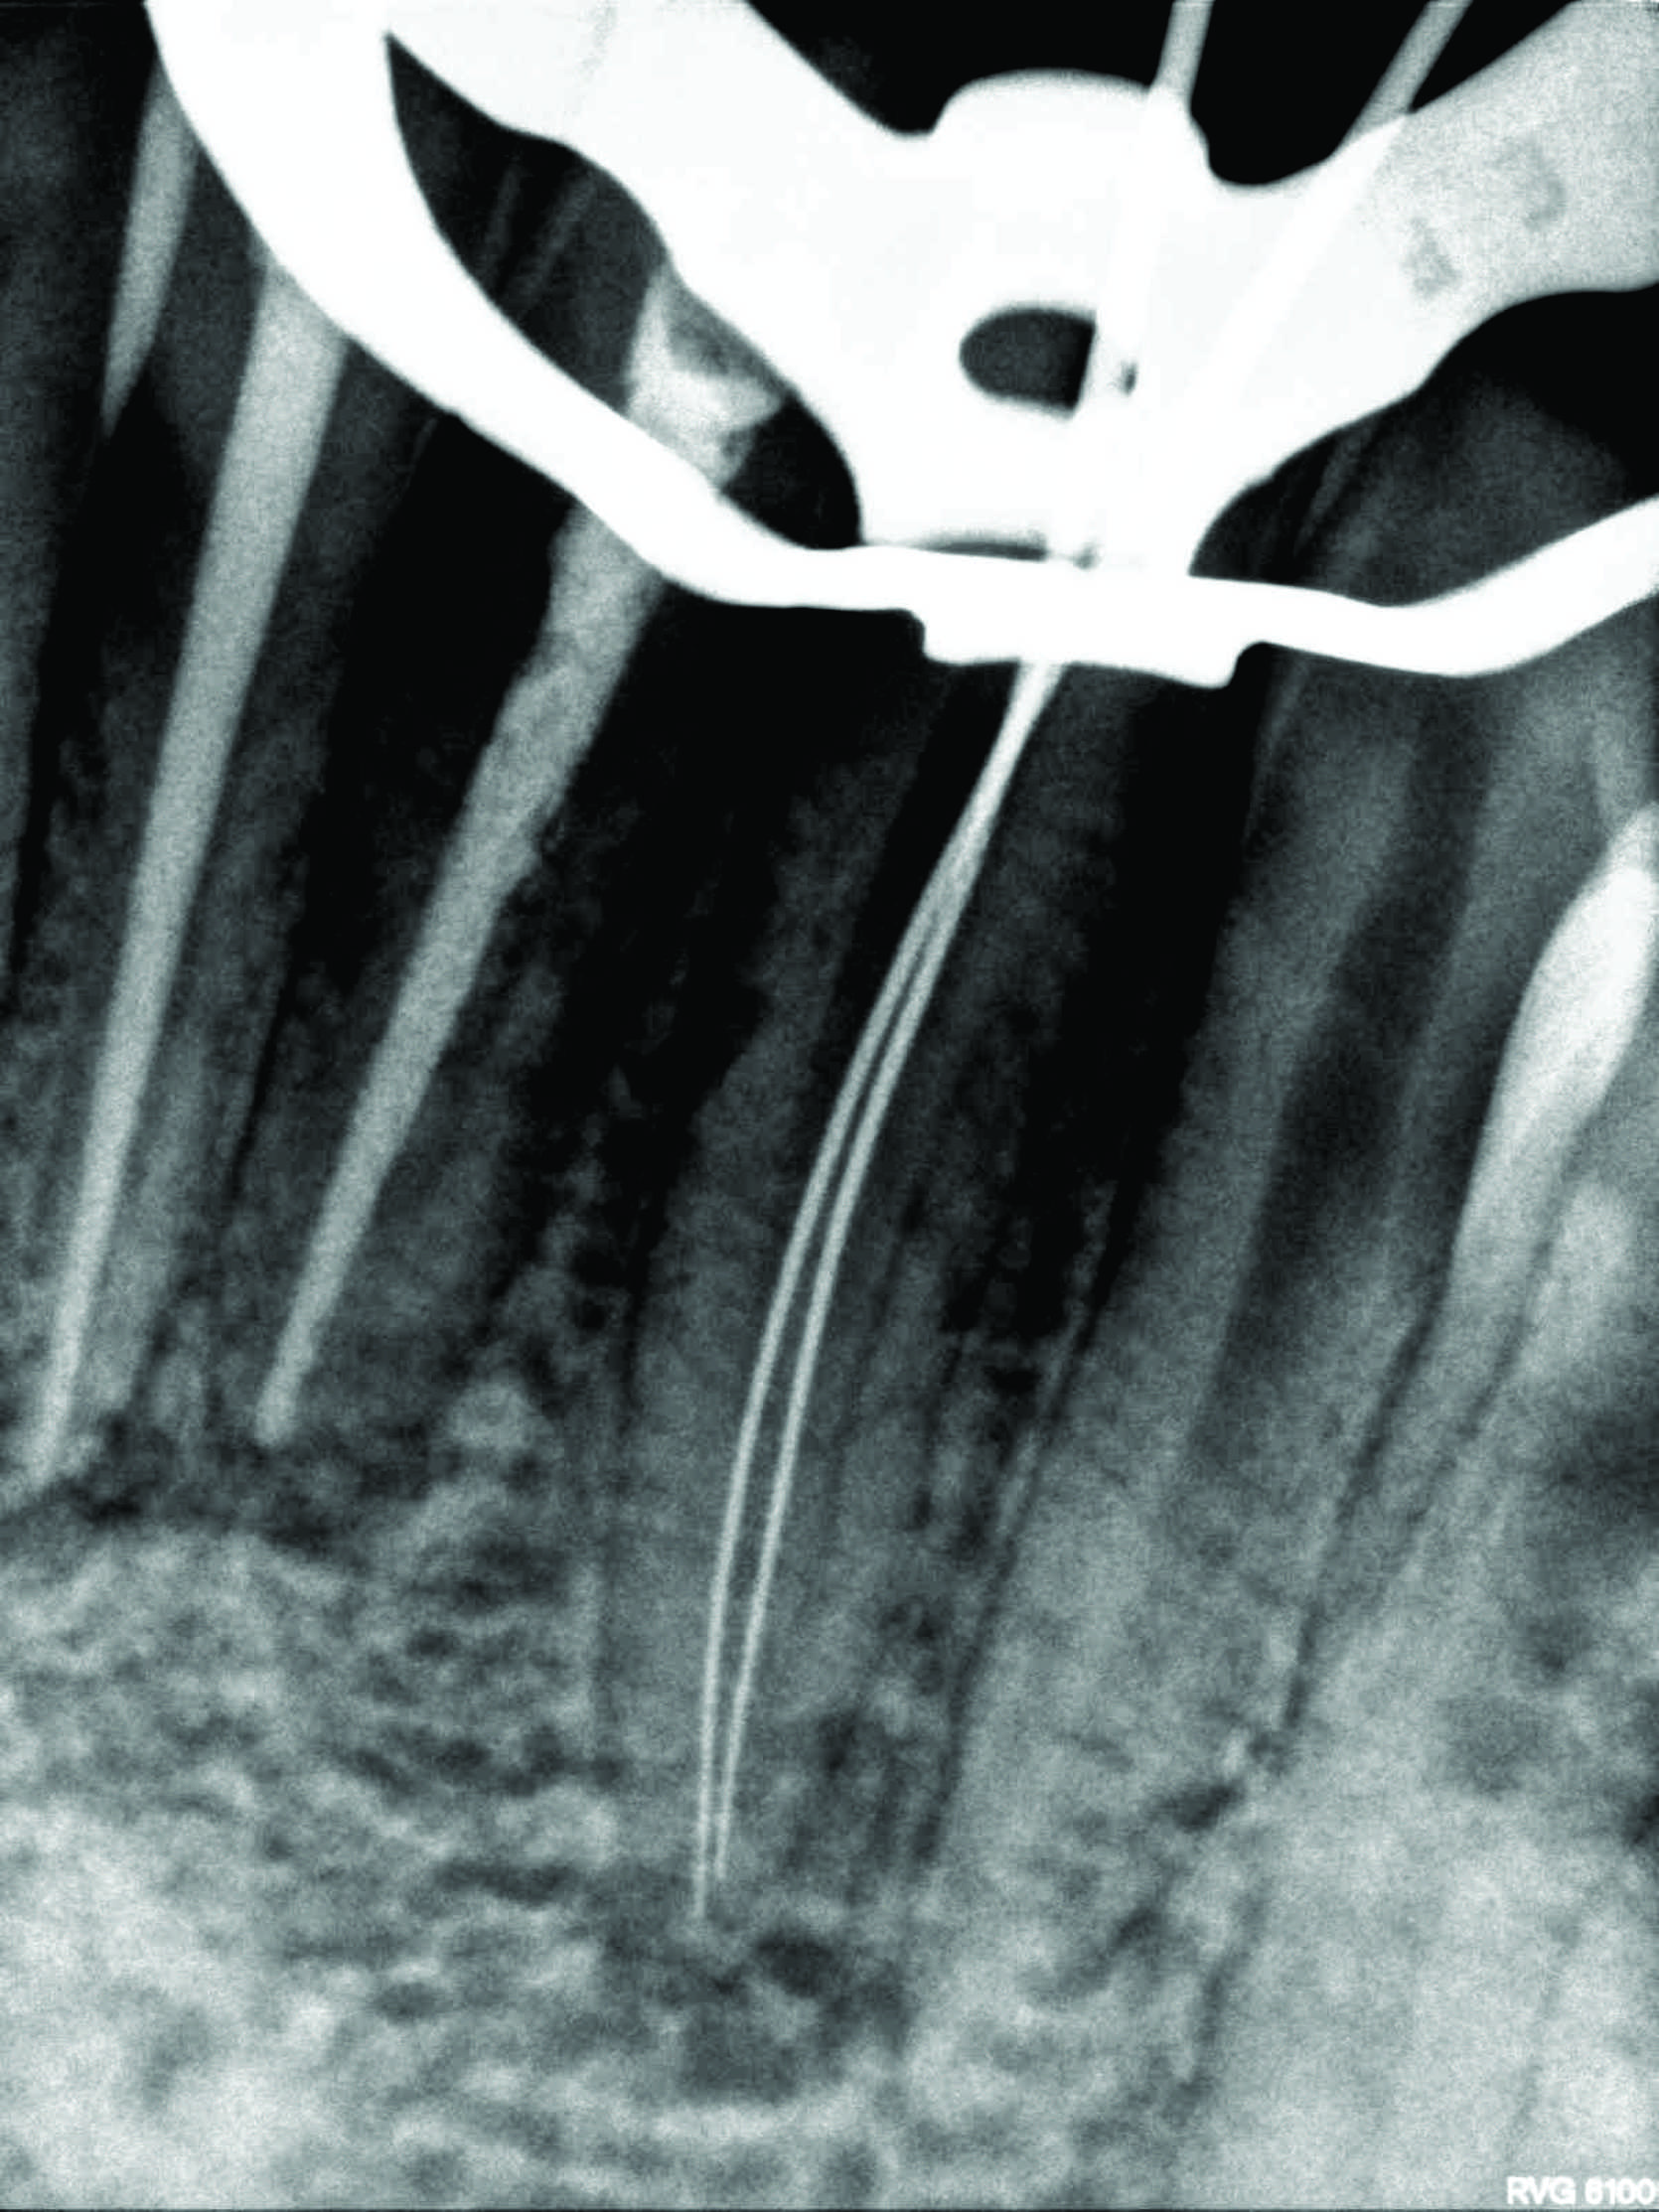

The patient had cutaneous opening of size 5mm × 6mm with purulent discharge in submental region. Patient had undergone three surgical excisions and multiple antibiotic regimens. Patient had a history of trauma due to fall six years back. A 30 number standard gutta-percha was used to trace the sinus tract and dental origin was confirmed radiographically. The tract led to in-between the root canal apices of both mandibular incisors. Treatment included non-surgical endodontic treatment with both mandibular central incisors and antibiotic coverage following bacterial culture of discharge. The pus culture showed Streptococcus anginosus which was found to be sensitive to penicillin. Patient was kept on 1-week course of oral amoxicillin-clavulanate along with root canal therapy.